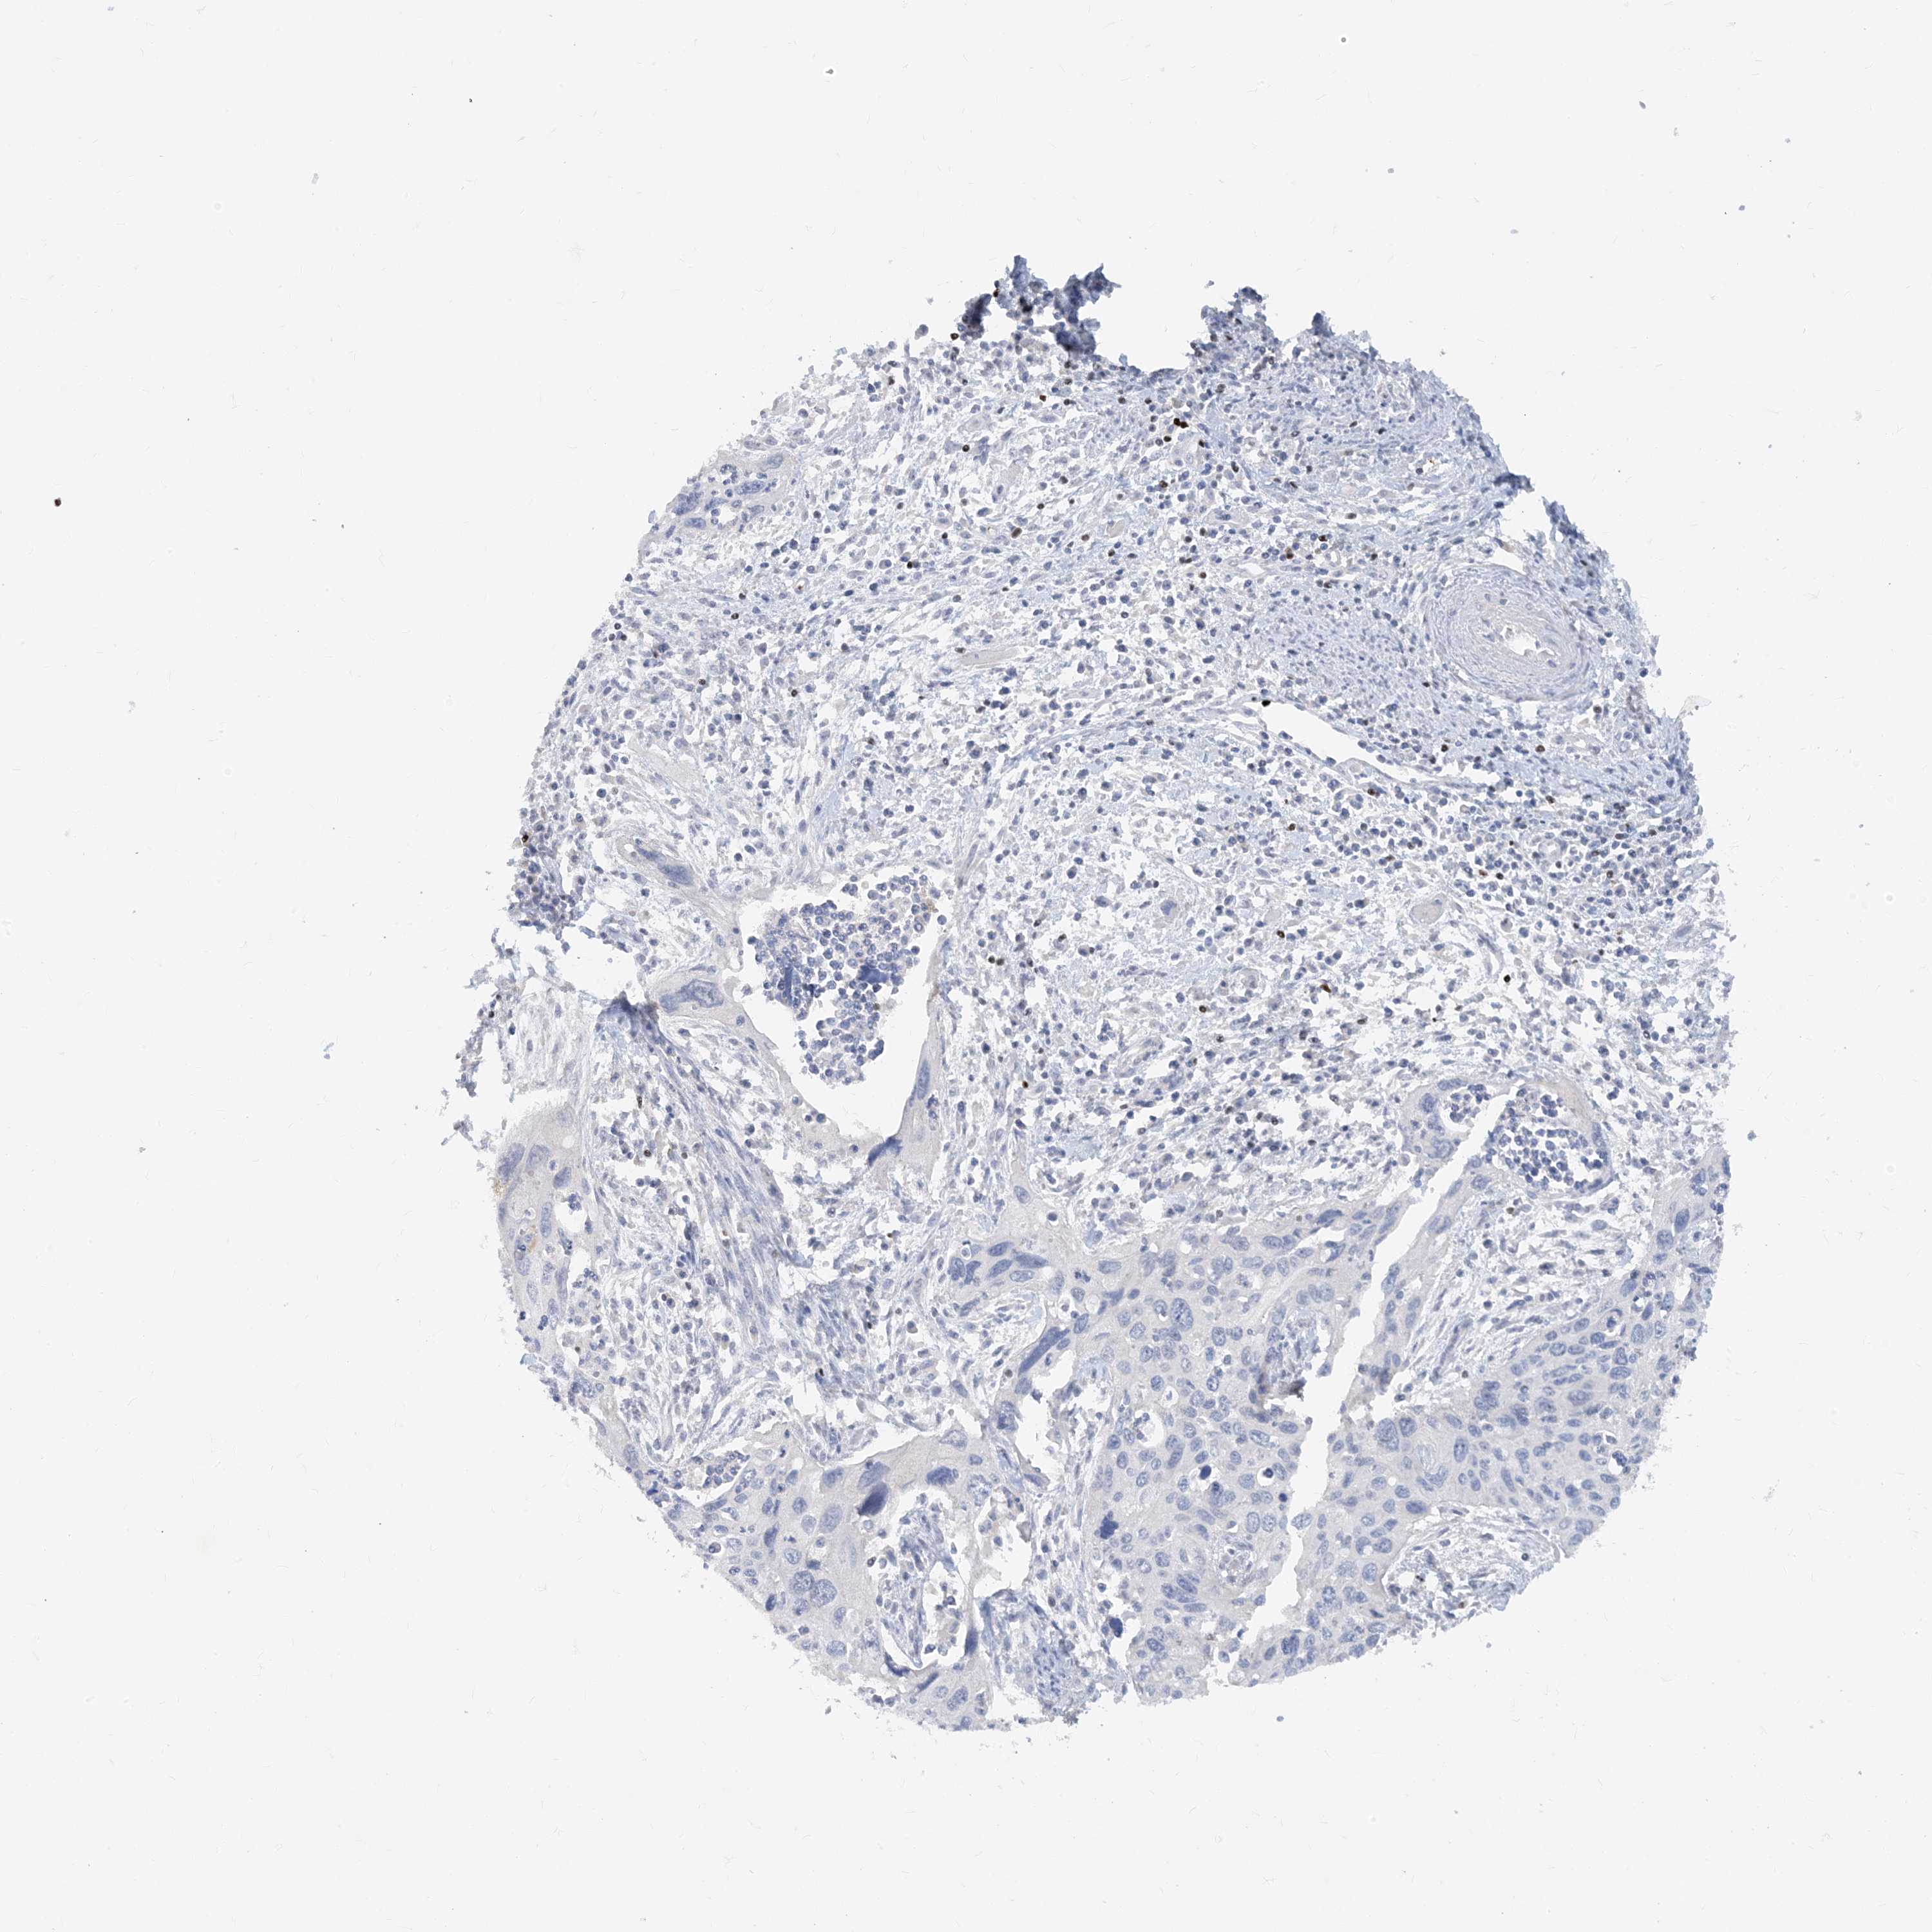

TBX21